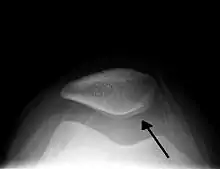

Image radio d'une hydarthrose du genou.

L’hydarthrose est l'accumulation anormale de liquide, spécialement de synovie, dans une articulation[1]. Cela survient essentiellement par augmentation de la sécrétion de synovie.